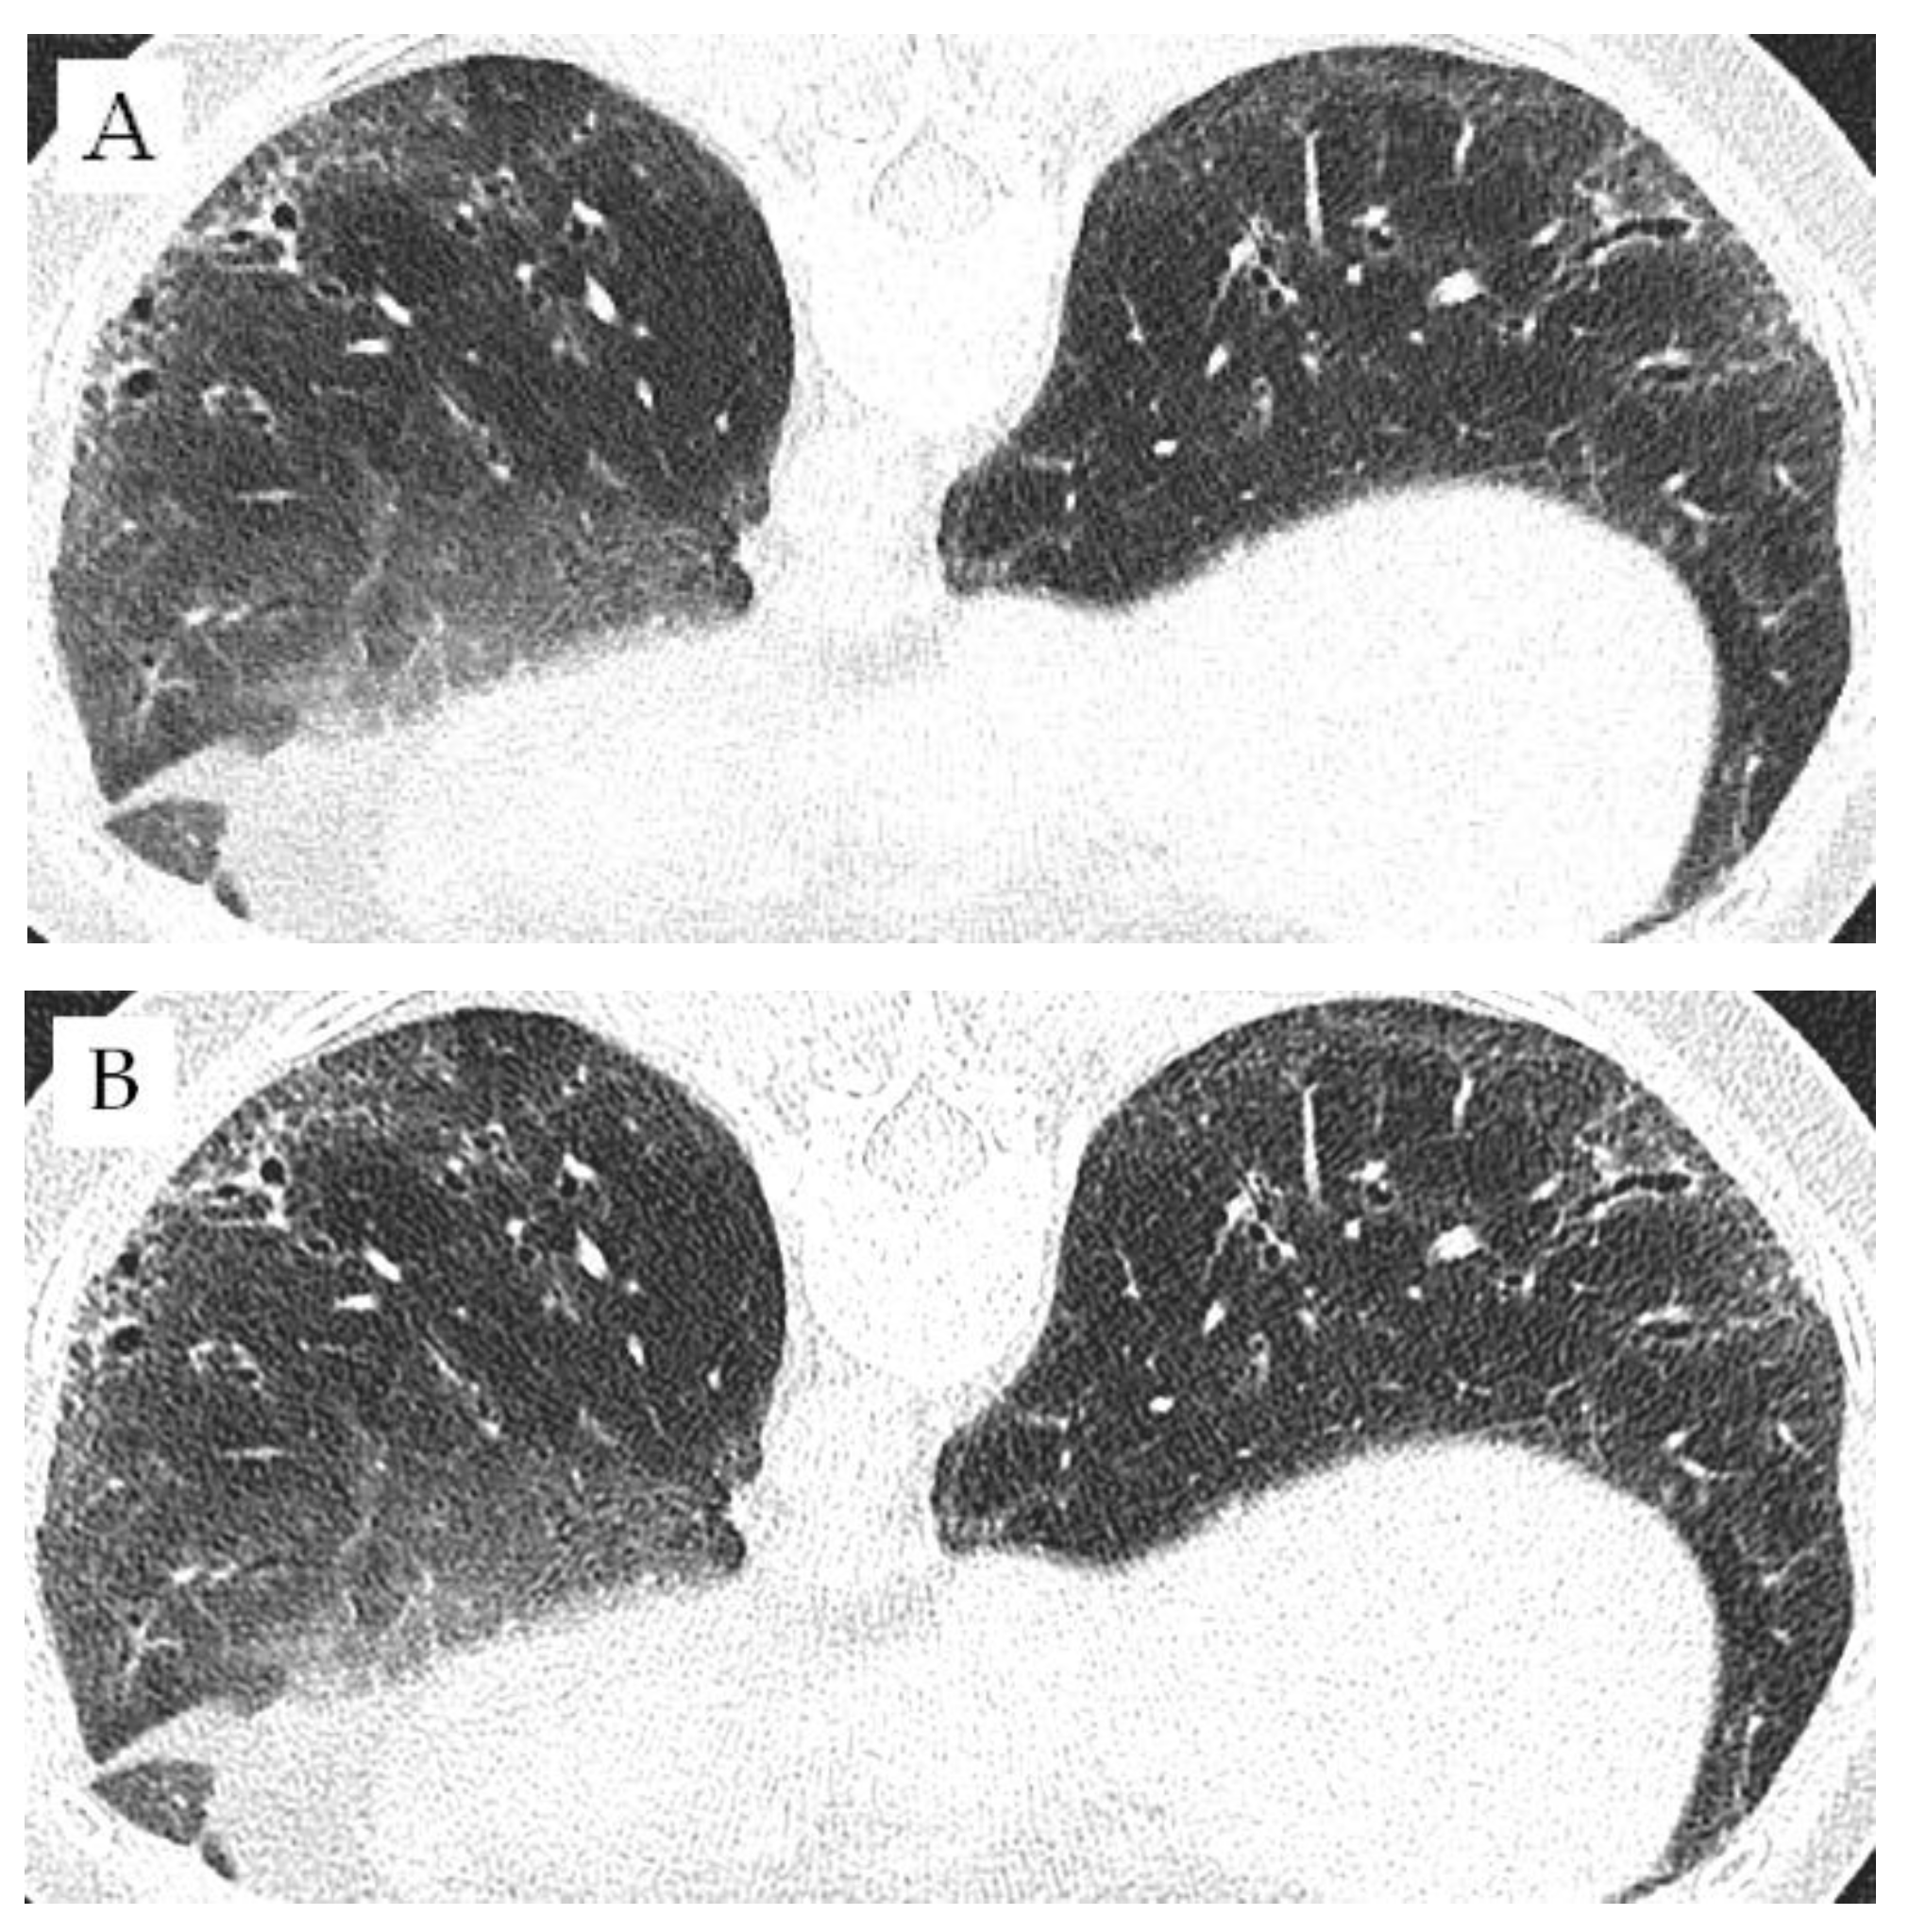

2.2. Image Acquisition

3.3. Comparison of Different Matrices

4. Discussion